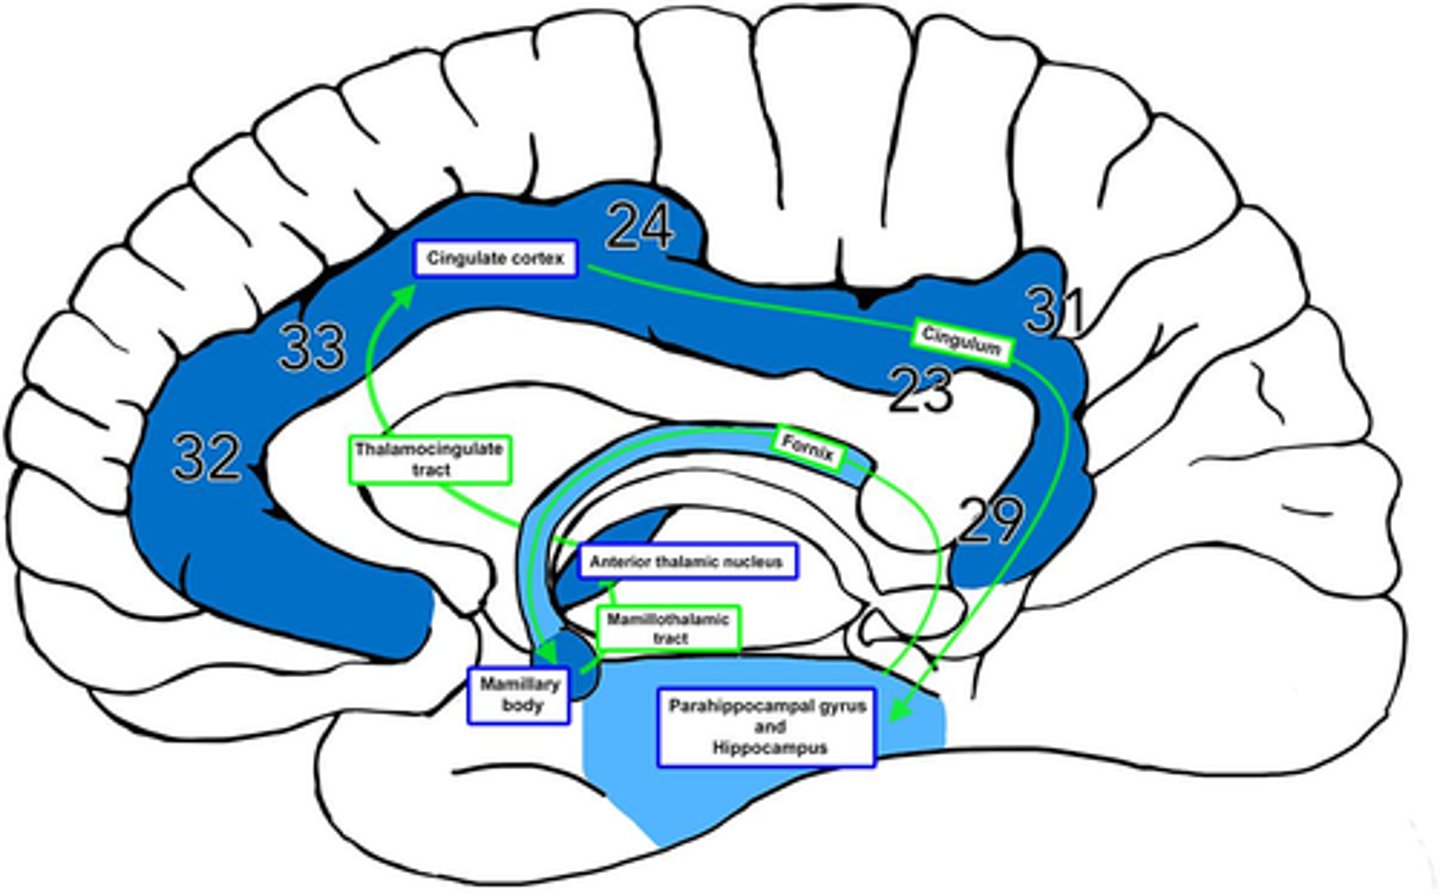

What is efferent to the anterior nuclei of the thalamus?

hippocampus via the cingulum

What is afferent to the anterior nuclei of the thalamus?

hippocampus and hypothalamus via mammillothalamic tract

What is the pathway from the hippocampus to the anterior nuclei of the thalamus?

1. hippocampus

2. fornix

3. mammillary nuclei

4. mammillothalamic tract

5. anterior nuclei (thalamus)

Where does the cingulate gyrus run?

superior to the corpus callosum